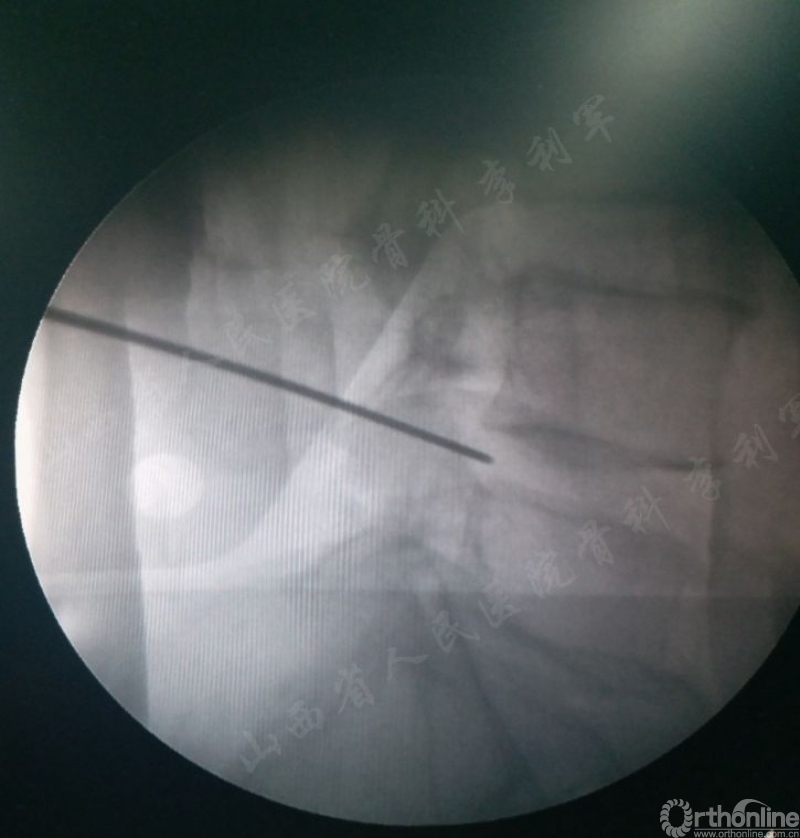

第一步:椎间孔穿刺,无需按标准靶点穿刺,只要穿刺针穿入椎间孔下半部分即可,只需要透视侧位片,不需要拍正位片,明显减少穿刺次数和透视次数。如图1

图1 穿刺针穿入椎间孔下半部分